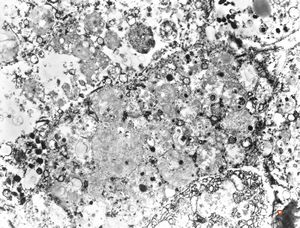

M,27y. | sea-blue histiocyte syndrome